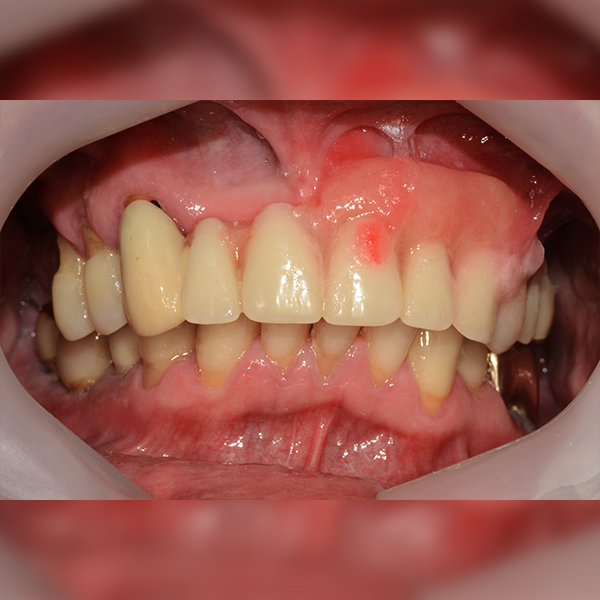

3. Тохиолдол.78 60-аад насны Шим*су 2017-12-12 / 2018-11-22

Oneday Шүдний эмнэлэг

Дээд эрүү / Бүтэн / Яс шилжүүлэн суулгах

Тохиолдол.78 60-аад насны Шим*су 2017-12-12 / 2018-11-22

After After

Before Before